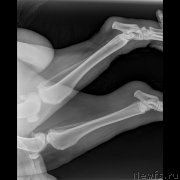

Второй ветеринар сделал ренген, где ничего не видно кроме начинающегося артроза.Опасения что слопал кость-отмели.

Сделали цифровой рентген в соседнем городе(Темиртау).Сейчас постараюсь его выставить.На мой взгляд не очень удачный.завтра наверное переделаем.

По клинической картине и по снимкам - спондилёз поясничного отдела позвоночника. Лечение: первые сутки дексаметазон 4 мг 3 раза /день или преднизолон, можно внутримышечно, и римадил 100мг 3 раза в день.